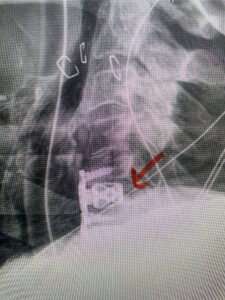

Another patient, a 77 year-old female, presents with pain, numbness, and weakness of her arms and difficulty with balance over a 6-month period. MRI revealed severe osteophytic disease at C5-C7 with cord compression (Fig. 4). Further work-up by fine-cut cervical CT to evaluate the nature of compression revealed a completely calcified osteophyte (Fig. 5). Although the patient had a good lordosis and a posterior cervical approach would accomplish an adequate decompression, we elected to perform a two-level anterior cervical discectomy and fusion. This particular osteophyte is formidable because of its size but the compression was all anterior and would be a less invasive approach. Fortunately, during the procedure, the patient had a fair amount of osteoporosis which allowed the osteophyte to be drilled and bit away with considerable ease. Interestingly, the C6 7 osteophyte which was more a sheet of osteophyte was more challenging to remove. In the end the decompression went well, and we placed two interbody devices filled with bone graft with plates at each level (Fig. 6). The patient had a nice recovery with immediate reduction of pain and numbness. This case demonstrates the importance of recognition of cervical myelopathy in its early stages. A significant reversal of function is generally the rule if the patient has appropriate correlative findings on exam and MRI, particularly with long tract distribution weakness development within a year time period.

Fig 6: Intraoperative lateral cervical x-ray demonstrating placement of interbody cages and plates